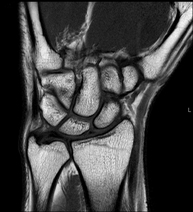

- RM Muñeca / carpo

Exploración para el estudio de lesiones en tendones músculos y articulación. Muy útil para la valoración de pequeñas fracturas inadvertidas, lesiones de ligamentos, y procesos inflamatorios y degenerativos (artritis y artrosis). Tiene una duración aproximada de 20 minutos. No emplea radiación ionizante.